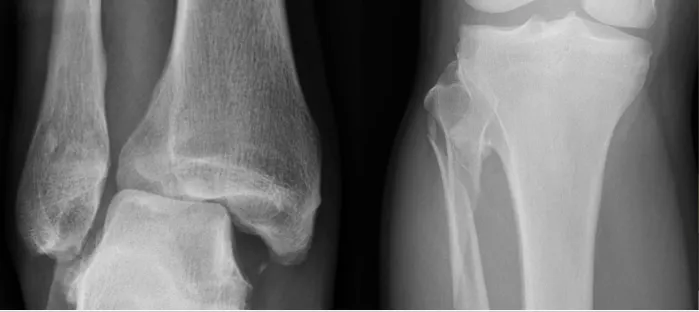

If injury proceeds along syndesmosis it involves proximal fibula = Maisonneuve Fracture

Always rule out Maisonneuve fracture in medial malleolar/ligamentous injury